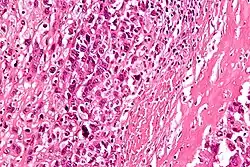

Au microscope la caractéristique de l'ostéosarcome est la présence d'ostéoïde (formation osseuse) dans la tumeur. Les cellules tumorales sont très pléomorphes (anaplasiques), certaines sont géantes, et de nombreuses mitoses sont atypiques. Ces cellules produisent des ostéoïdes décrivant des travées irrégulières (amorphes, éosinophiles / roses) avec ou sans calcification centrale (hematoxylinophilic / bleu, granulaire) - os de la tumeur. Les cellules tumorales sont incluses dans la matrice ostéoïde. Les ostéosarcomes peuvent présenter des cellules géantes ostéoclastiques comme multinucléées[7].